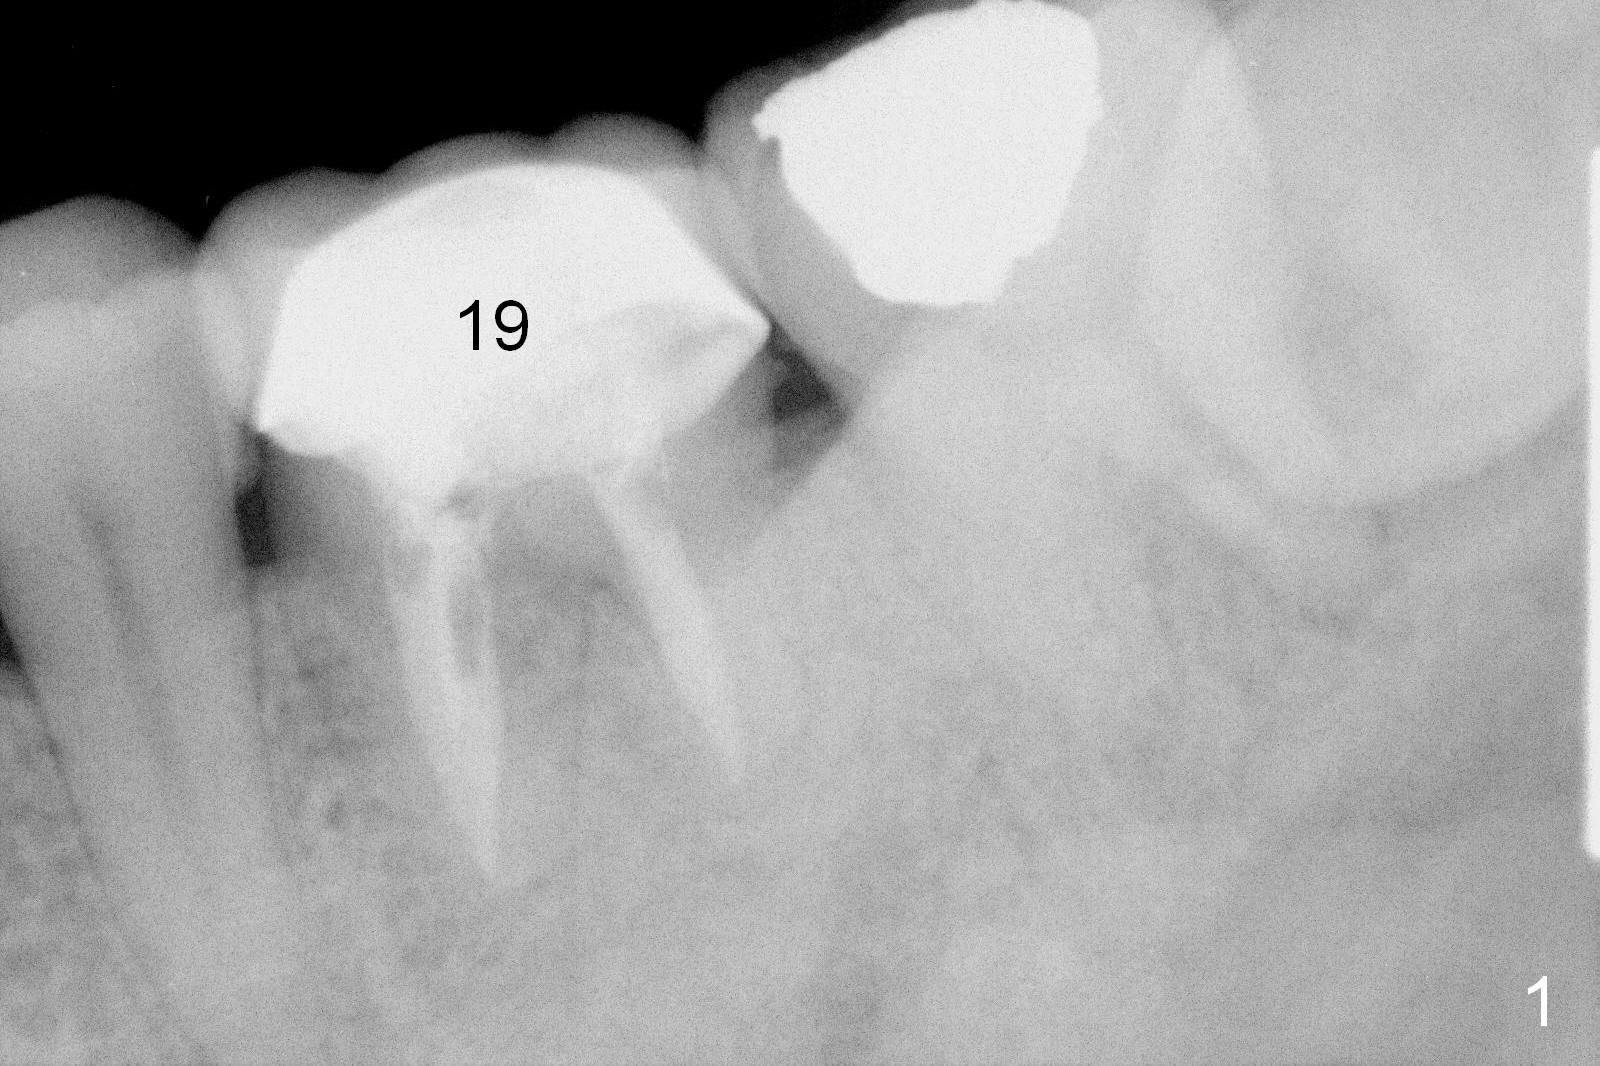

The tooth #19 of a 54-year-old man (FJ) looked normal 2.5 years ago (Fig.1).  The patient returns because of 3 fistulae developing around the mesial root of the tooth.  Recent PA shows a large radiaolucent defect (Fig.2,3).  To place an implant in the middle of the edentulous space, initial osteotomy should be distal because of the large mesial defect.